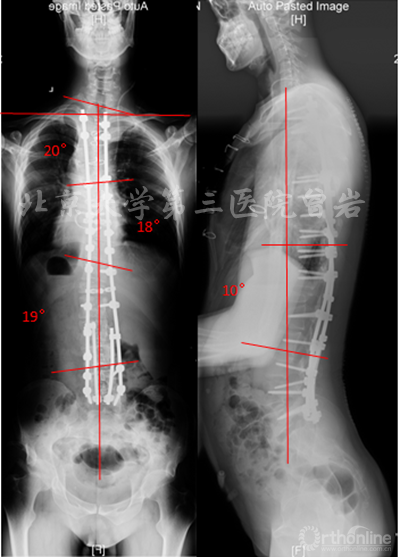

术后X线(图13):侧凸上胸弯Cobb 20°,下胸弯Cobb 18°,胸腰弯Cobb 19°,后凸角度10°,冠状位和矢状位平衡维持良好,双肩等高。

图13